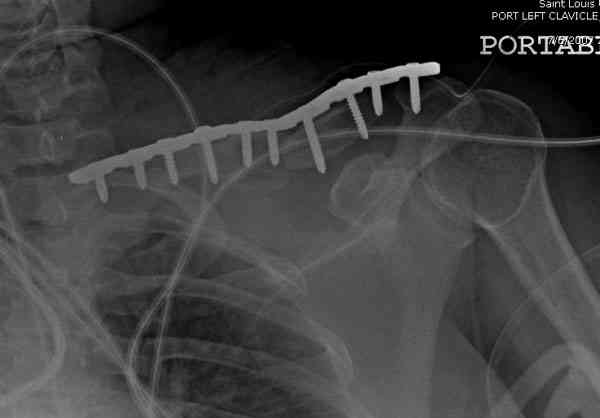

Недавно разбирали случай ложного сустава.

45 летная женщина после автоаварии, алкоголь 163 и 20 летним стажем курения.

Консервативное лечение, через 8 мес. операция Rockwood pin с костной пластикой в нашем городе другим врачом. После 8 недели падение, гвоздь удален оперирующим хирургом, больная направлена к нам. Фиксация реконструктивной пластиной с трикортикальным графтом, добавлен BMP-2. Для стабилизации фиксацию провели через акромион.

Вот уже два месяца больная также продолжает жаловаться на боли, буквально на днях удалили акромиальную часть пластины с специальной пилой с алмазным покрытием для медицинского металла. До сих пор судьба ложного сустава неизвестна....

Второй случай тоже недавно оперирован по поводу

ложного сустава, в марте травма, через 4.5 половиной

операция..